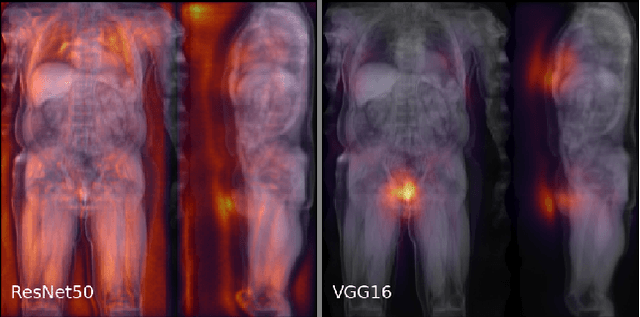

Abstract:Purpose: To enable fast and automated analysis of body composition from UK Biobank MRI with accurate estimates of individual measurement errors. Methods: In an ongoing large-scale imaging study the UK Biobank has acquired MRI of over 40,000 men and women aged 44-82. Phenotypes derived from these images, such as body composition, can reveal new links between genetics, cardiovascular disease, and metabolic conditions. In this retrospective study, neural networks were trained to provide six measurements of body composition from UK Biobank neck-to-knee body MRI. A ResNet50 architecture can automatically predict these values by image-based regression, but may also produce erroneous outliers. Predictive uncertainty, which could identify these failure cases, was therefore modeled with a mean-variance loss and ensembling. Its estimates of individual prediction errors were evaluated in cross-validation on over 8,000 subjects, tested on another 1,000 cases, and finally applied for inference. Results: Relative measurement errors below 5\% were achieved on all but one target, for intra-class correlation coefficients (ICC) above 0.97 both in validation and testing. Both mean-variance loss and ensembling yielded improvements and provided uncertainty estimates that highlighted some of the worst outlier predictions. Combined, they reached the highest quality, but also exhibited a consistent bias towards high uncertainty in heavyweight subjects. Conclusion: Mean-variance regression and ensembling provided complementary benefits for automated body composition measurements from UK Biobank MRI, reaching high speed and accuracy. These values were inferred for the entire cohort, with uncertainty estimates that can approximate the measurement errors and identify some of the worst outliers automatically.